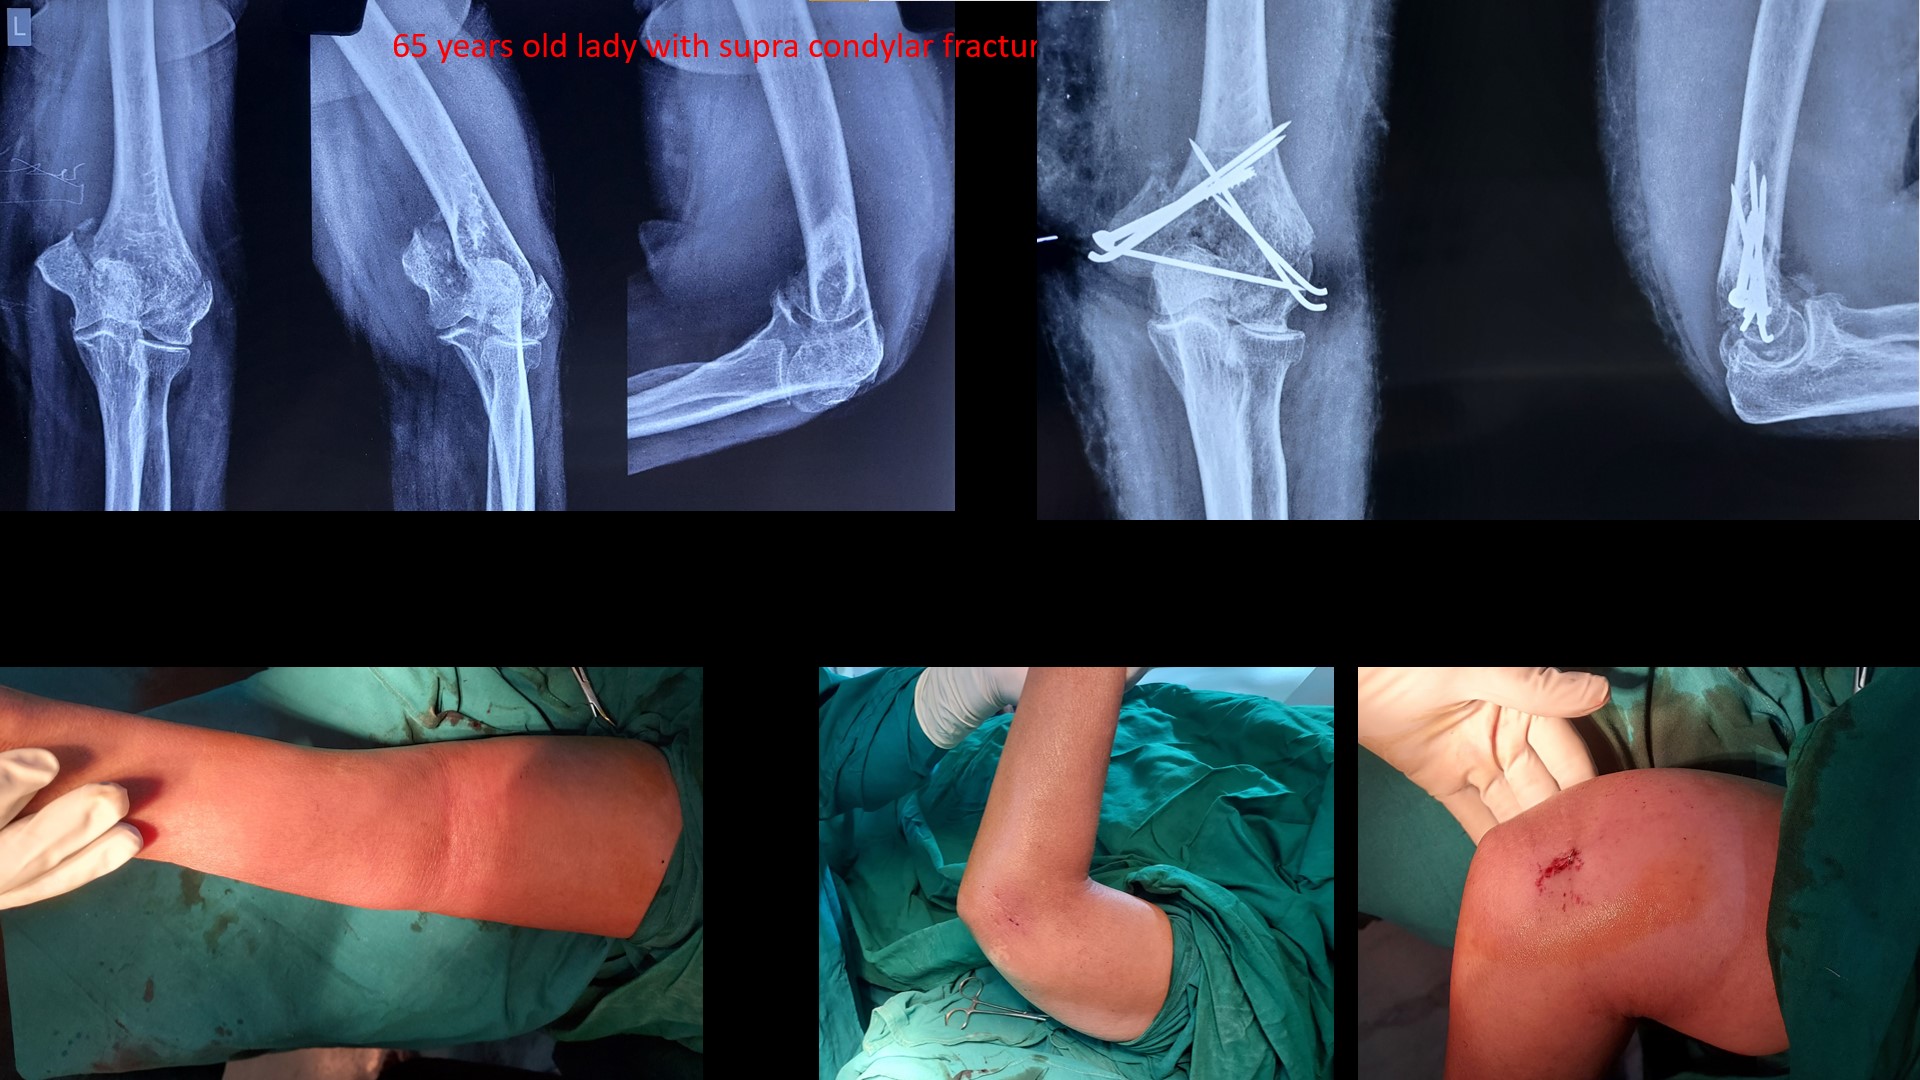

SUPRACONDYLAR #